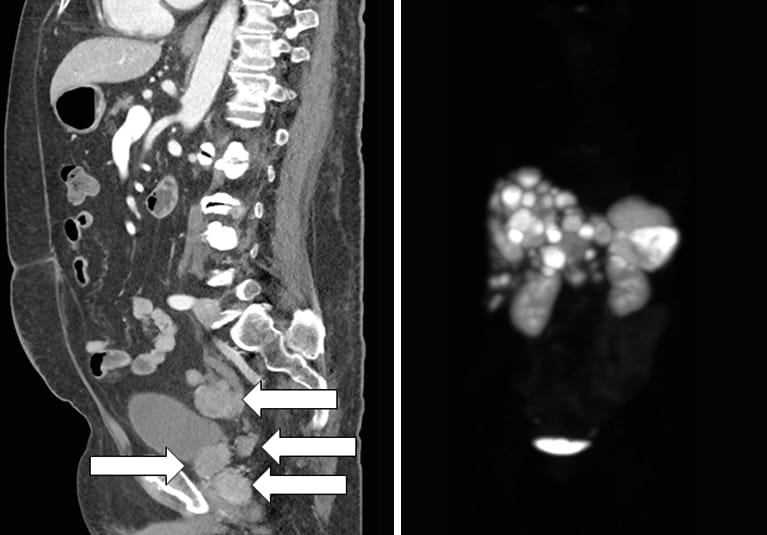

Contrast-enhanced CT scan sagittal image showing prostatic mass and multiple metastases (arrows).

Prior to the Mayo Clinic evaluation, the patient had an abdominal CT scan performed for resistant hypertension. The scan revealed prostate enlargement with seminal vesicle invasion and multiple areas of intraperitoneal metastases. Prostate biopsy showed two distinct diagnoses of small cell carcinoma and prostate adenocarcinoma. Further laboratory studies confirmed severe corticotropin (ACTH)-dependent hypercortisolism, which was determined to be due to ectopic ACTH production from prostate small cell carcinoma.